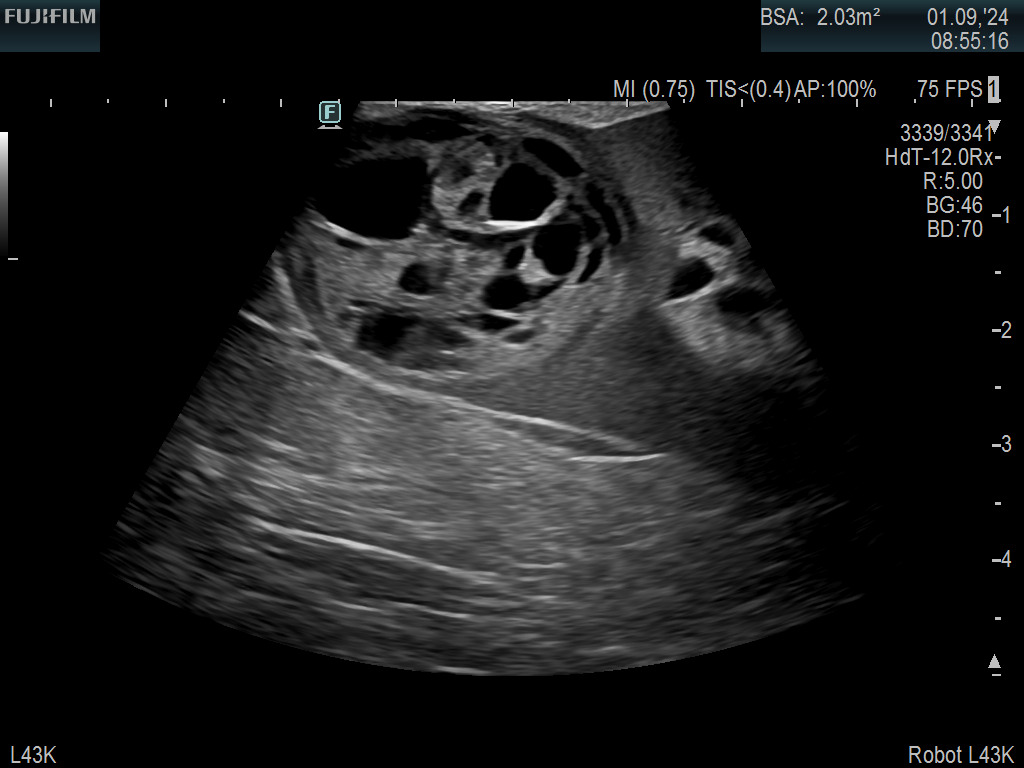

Robotic Surgery on Kidney with Complex Mass using the L43K Drop-In

Ideal for liver and kidney scanning with optimum location and design of grasping mechanism allowing for full wrist articulation.